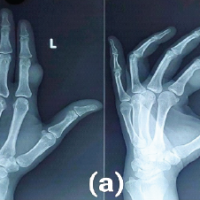

None of the patients experienced post-operative knee or hip stiffness after undergoing combination fixation with an intramedullary nail and derotation plate. X-rays of the patient with follow-ups at 3 months and 6 months(Fig. 1, 2, 3, 4).

Figure 1: Showing pre-operative X-rays.